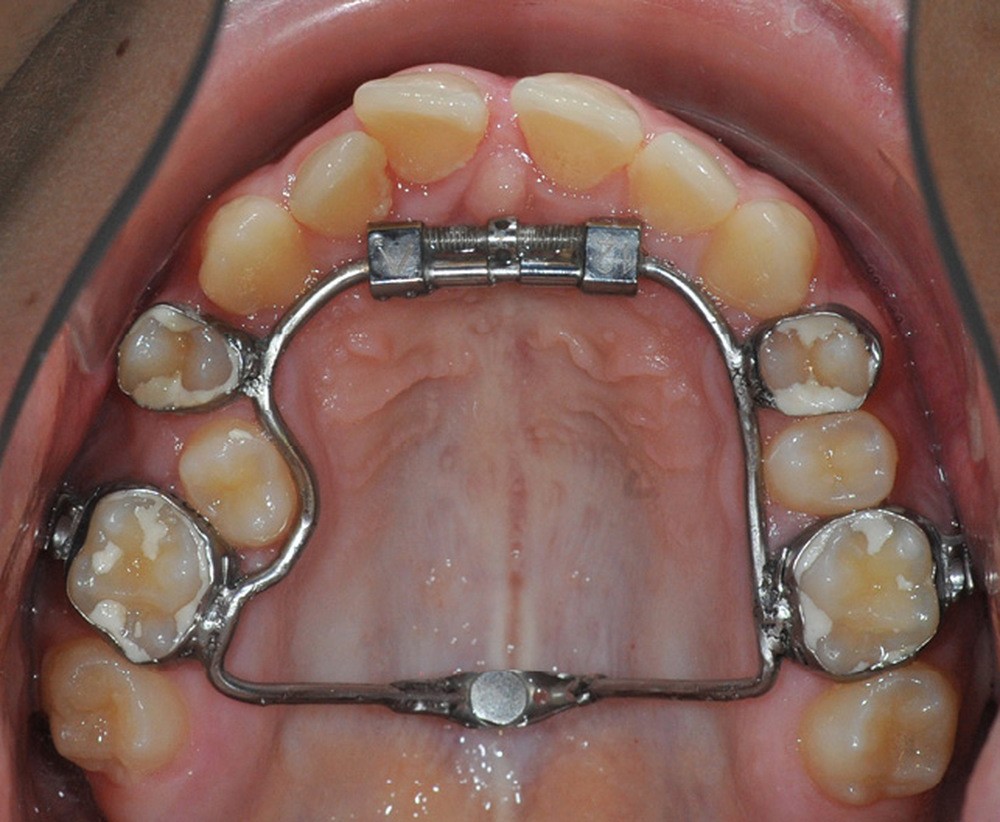

La matinée s’achèvera par le traitement de la dysharmonie dent-arcade par des techniques chirurgicales originales et novatrices : l’expansion transversale maxillo-mandibulaire (Dr Jean-Luc Ouhioun, fig. 2a-h) et la distraction sagittale du bloc incisivo-canin « front-block de Triaca » (Dr Olivier Esnault).

À côté de la coopération moindre qu’ils exigent, les ancrages squelettiques présentent également l’avantage de répondre à des indications très variées : correction des sourires gingivaux (Dr Skander Ellouze, fig. 3a-c), distalisation ou mésialisation molaire, supports pour les masques faciaux, mini transpalatin sur vis après expansion, ressorts de rétraction pour mettre en place les canines incluses sans léser les racines des dents adjacentes [3] (Dr Stéphane Renger, fig. 4) ou appareils d’expansion maxillaire (Dr Hans Winsauer, Dr Guido Sampersmans, fig. 5a-c)…